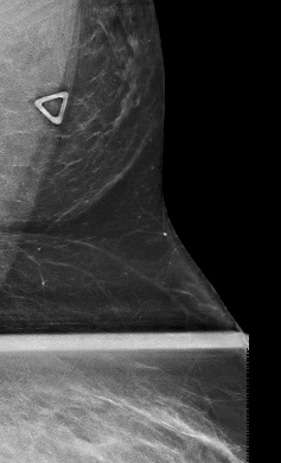

On mammography, accessory breast tissue in the axilla presents as variable quantities of fibroglandular densities scattered amongst fat, which is separate from the main pectoral breast tissue2 (Fig. 1). This appearance should be distinguished from the axillary tail of Spence, which is fibroglandular tissue that is contiguous with the main duct system of the breast tissue and extends into the axilla.1 Of note, if a focal asymmetry in the axilla is new, changed, or identified on a baseline study, a diagnostic exam should be performed to rule out a pathologic process.2

Case: Accessory  Breast Tissue Figure 1

Figure 1: Spot compression mammogram of the left axilla shows a patch of fibroglandular tissue within the fat of the axilla, which is separate from the pectoral glandular tissue.